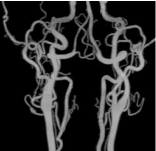

下肢動脈VR -

下肢動脈MIP -

下肢動脈拡大VR